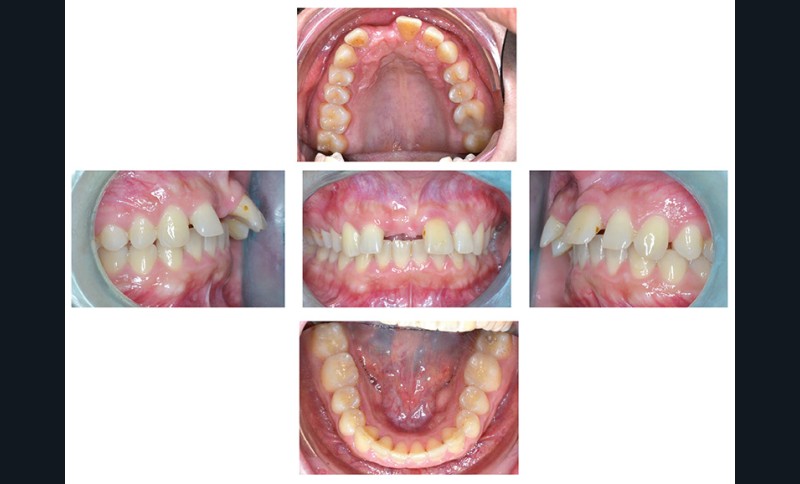

Charlotte présente donc une absence de 11, un surplomb et un recouvrement augmentés associés à une retromandibulie. La patiente a un profil convexe, hypodivergent avec une proalvéolie maxillaire et une classe II d’Angle. (fig. 1a à h). La radiographie panoramique confirme l’absence de 11 et la téléradiographique de profil, révèle une classe II squelettique (ANB : 6°, AoBo : 9 mm) par rétromandibulie ainsi qu’une proalvéolie maxillaire prononcée.

(I/Na : 40° I-Na : 7 mm) (fig. 2a et b).